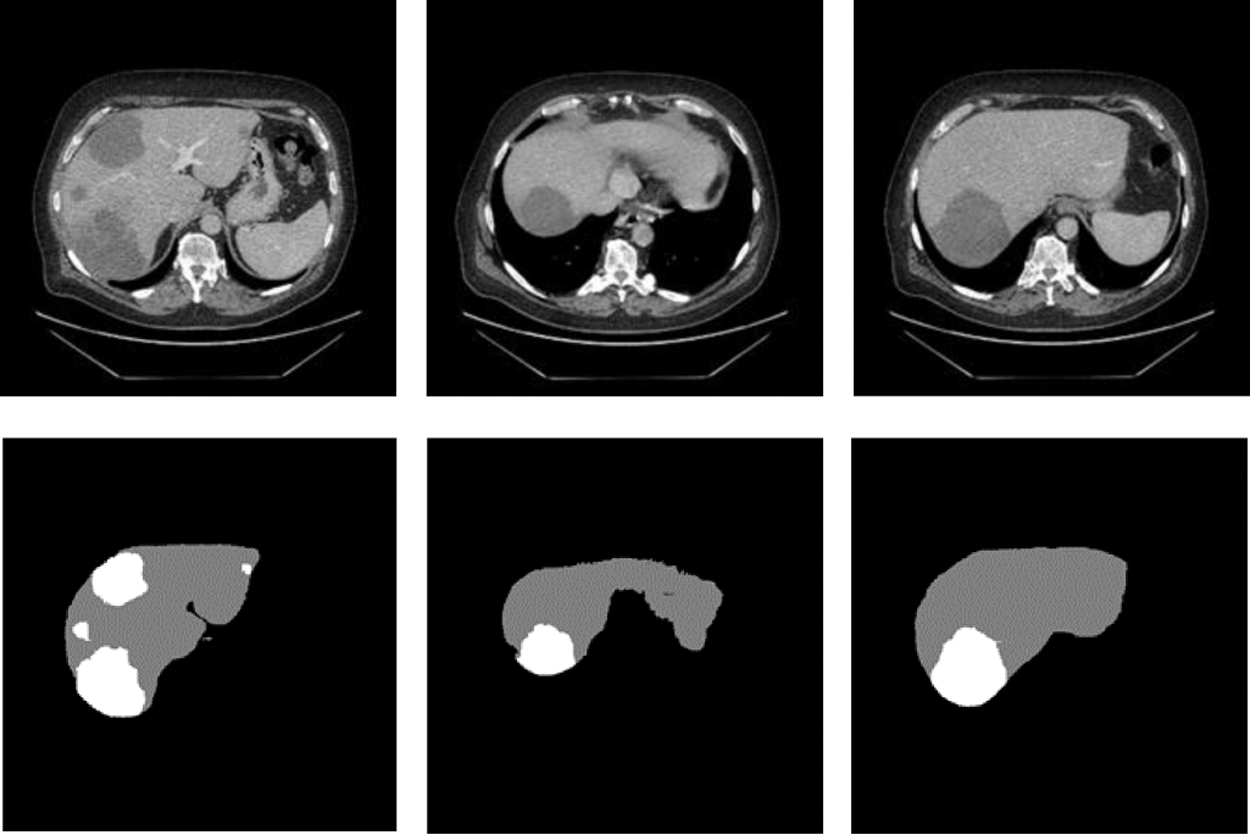

We processed the public dataset about Liver Tumor Segmentation (LITS) provided by Coda Lab. There were hundreds of CT image slices for each patient. The data which have been Pre-processing can be shown in the Fig. 6. The abdominal CT images and labels of cases used in this research all from LITS which were manually annotated by some radiologists. From these 131 groups of cases, we selected 118 groups of cases as training set and tumor labels and 25 groups of cases for testing. In addition, we set to extract 45 valid slices in each group of cases.

Figure 6: The slices used to train

In order to prove that the two new modules designed in this network and the adaptive weighted cross-entropy loss function achieved superior results for liver and tumors segmentation, the ablation experiments were first performed and the trained model was tested on the test set, and the segmentation results are shown in the Fig. 6. It indicated the test results of the proposed network for liver and tumors segmentation together with the results of manual annotation by experts.

From Fig. 7, we can see that the segmentation results obtained from the model designed in this paper were very close to expert annotation images, and this method can effectively optimize the border details of liver and tumor and solve low contrast and complex areas problems.

Figure 7: Raw, ground truth and segmentation results on the test image